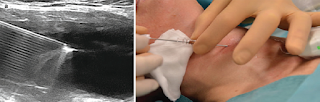

Percutaneous ethanol injection for benign cystic thyroid nodules

Aim The aim of this study was to evaluate the efficacy and safety of percutaneous ethanol injection (PEI) in managing predominantly cystic benign thyroid nodules in euthyroid individuals and avoid complication of surgery, provide symptomatic, cosmetic improvement, decrease the hospital stay and rapid recovery. Patients and methods The study is an experimental clinical trial. Twenty patients (34.20 ± 7.52 years; 60% women) with symptomatic benign thyroid cysts were included. In all cases, cytology before treatment, thyroid function before and after PEI, maximum cyst diameter, and volume were determined. PEI was conducted using 99% sterile ethanol, and pain perceived by the patients was assessed. After follow-up, final cyst diameter and volume were determined. Results The patients mean age was 34.20 ± 7.52 years, and 60% were females. A single session of PEI was required to complete the procedure. Mean initial maximum cyst diameter was 4.3 cm. Mean reduction in the cyst volume was 94.38%±4.04. During PEI, 40% of patients experienced pain. No complications of PEI were observed. After 6 months of follow-up, cysts were reduced more than 95% in 75% of patients, and reduced less than 95% in 25% of patients. Conclusion PEI can be the first-line treatment of benign thyroid cysts. It is a highly efficacious and safe technique with improvement in clinical conditions, with very low recurrence rate, and with no complications except pain associated with injection, which can be managed by analgesic.

Percutaneous ethanol injection for benign cystic thyroid nodulesp. 110